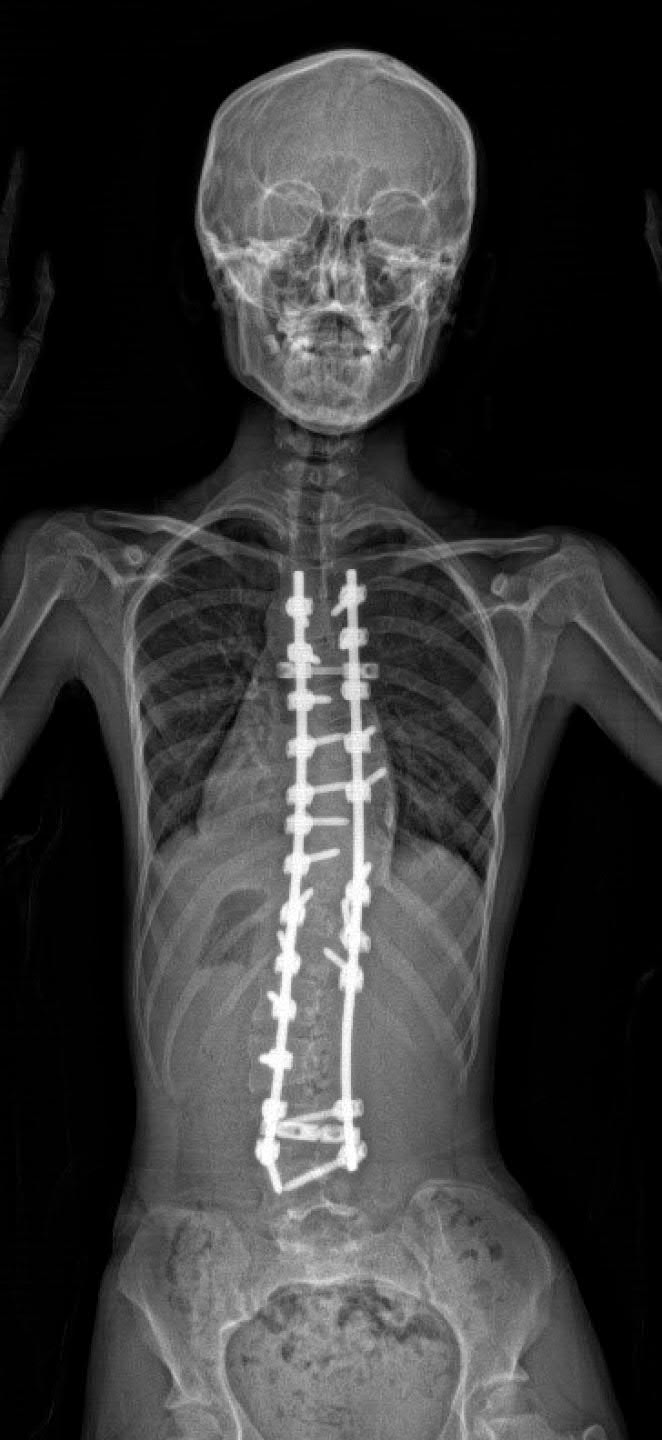

患者在接受脊柱側(cè)彎治療手術(shù)後的X光片

研究團(tuán)隊亦邀請了參與過脊柱側(cè)彎矯正手術(shù)的羅女士在發(fā)布會上分享經(jīng)驗。她介紹小學(xué)五至六年級期間開始出現(xiàn)有關(guān)癥狀,直至婚前體檢期間她獲醫(yī)生告知脊柱側(cè)彎有壓迫心臟風(fēng)險,最後決定進(jìn)行手術(shù)治療,覆診時未見有後遺癥。(實習(xí)記者 邱之璘 港大醫(yī)學(xué)院提供圖片)